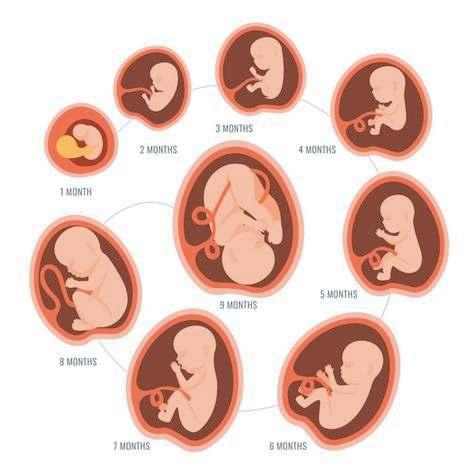

EMBARAZO

Este es el período que transcurre entre la implantación del cigoto en el útero hasta el momento del parto en cuanto a lo significativos cambios psicológicos, metabólicos e incluso morfológicos.

Que se producen en la mujer encaminados a proteger, nutrir y permitir el desarrollo del feto, como la interrupción de los ciclos menstruales o el aumento del tamaño de las mamas para preparar la lactancia el embarazo tiene una duración de 40 semanas